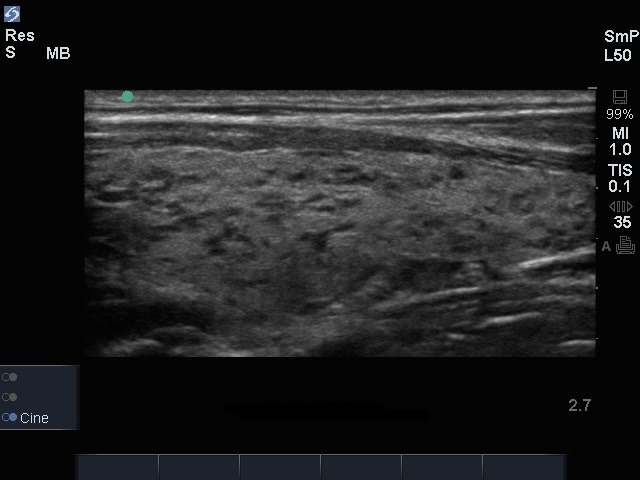

甲状腺异常矢状面图像